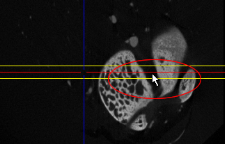

- Adjust the thickness of the slab rendering by dragging the dotted lines of the slab thickness markers shown in the other MPR scene views of the dataset.